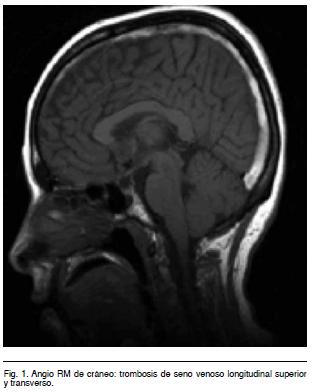

Tomografía Computarizada (TC) de cráneo: normal. Angio Resonancia Magnética (RM) de cráneo (Figura 1): trombosis de seno venoso longitudinal superior y transverso. Tratamiento: Heparina de Bajo Peso Molecular (HBPM) a dosis de anticoagulación (dosis ajustada) y superposición con Warfarina. Buena evolución. Estudios de trombofilia (TF): heterocigota para Factor (F) II G20210A.